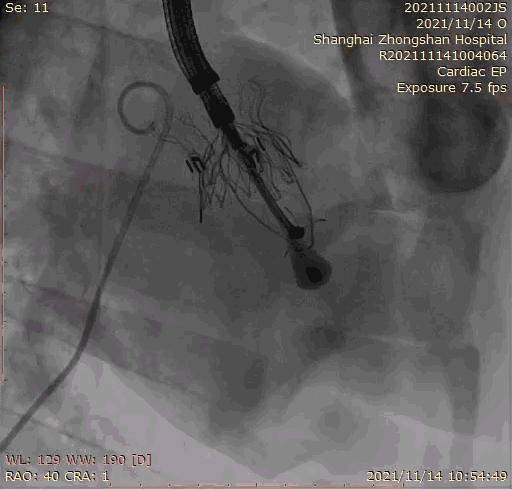

本次臨床前研究經(jīng)右側(cè)頸靜脈置入LuX-Valve Plus輸送系統(tǒng)可調(diào)彎鞘管,在DSA及超聲引導(dǎo)下將人工三尖瓣瓣膜植入到原有三尖瓣位置,利用獨特的錨定技術(shù)將人工瓣膜支架可靠固定在預(yù)定的位置。